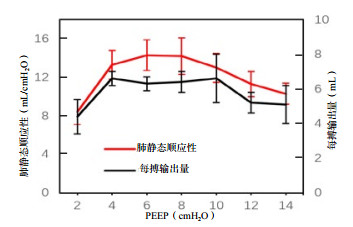

造模前后FAC、SV基线水平时差异均有统计学意义(P < 0.05),提示是ARDS本身造成的影响。PEEP递增时,造模后的SV、TAPSE低于造模前,差异有统计学意义(P < 0.05)。PEEP递增时,造模后TAPSE、SV先增大后减小,差异有统计学意义(P < 0.05)。其中SV分别在PEEP =4 cmH2O及10 cmH2O时最大;TASPE变化反复波动,见表 2。如图 2所示,造模后SV和Cstat随PEEP增加其变化趋势比较,SV和Cstat呈现同向变化关系。

| 图 2 造模后不同PEEP时每搏输出量和肺静态顺应性变化比较 Fig 2 Comparison of SV and Cstat at different PEEP after modeling |